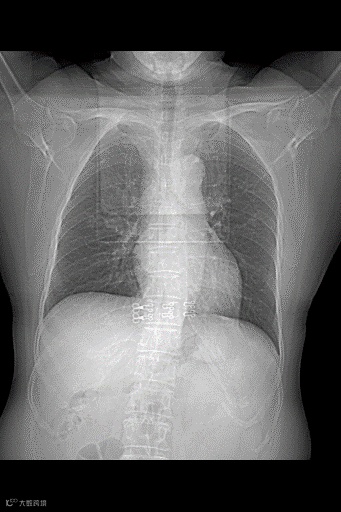

这是一位63岁女性的胸片,初诊时双肺没有发现大的病灶,表现基本正常。